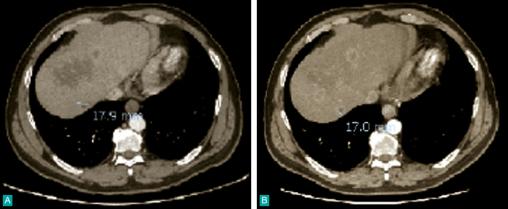

Métastases hépatiques multiples

2. Métastases hépatiques multiples